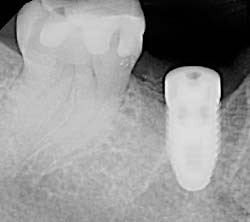

Using the most advanced dental technology possible is just as important as staying up-to-date on the latest treatment techniques. Because our practice is dedicated to providing you with the safest and most convenient treatment options available, we utilize advanced digital X-ray technology in our office.

Digital X-rays provide several advanced imaging options, designed to save time, provide clearer dental photos, and expose patients to less radiation than with traditional X-ray technology.